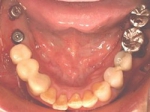

術後、左下奥2本インプラント(鏡像)